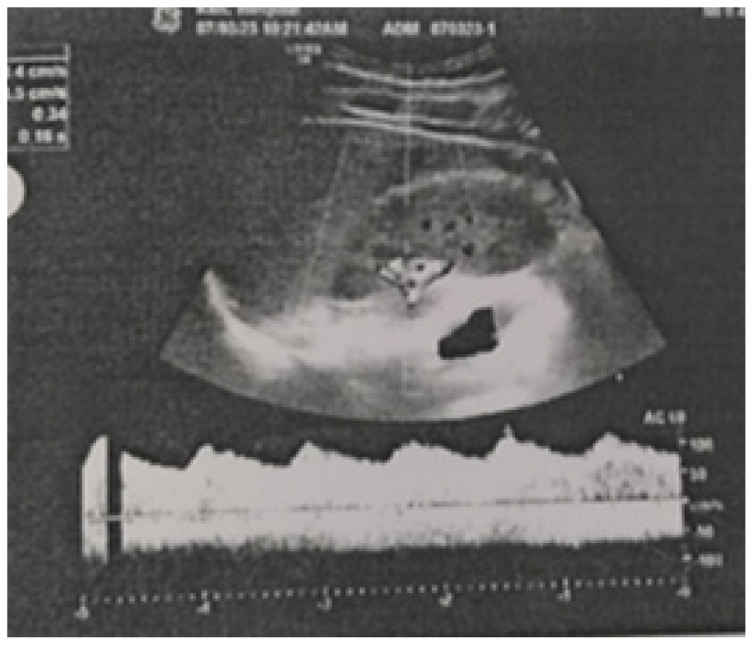

Case presentation: A 20-year-old patient was admitted to our hospital as he complained of headache and palpitations since one week. On examination, the blood pressure in his right upper limb was 180/100 mmHg. The volume of the femoral and the dorsalis pedis pulses was found to be reduced bilaterally. The patient was started on antihypertensive medication labetalol 10 mg injection intravenously immediately. After clinical suspicion and a series of investigations, the patient was diagnosed with severe CoA, distal to the origin of the left subclavian artery via computed tomography (CT) aortogram. The patient was managed by coarctoplasty with stenting.